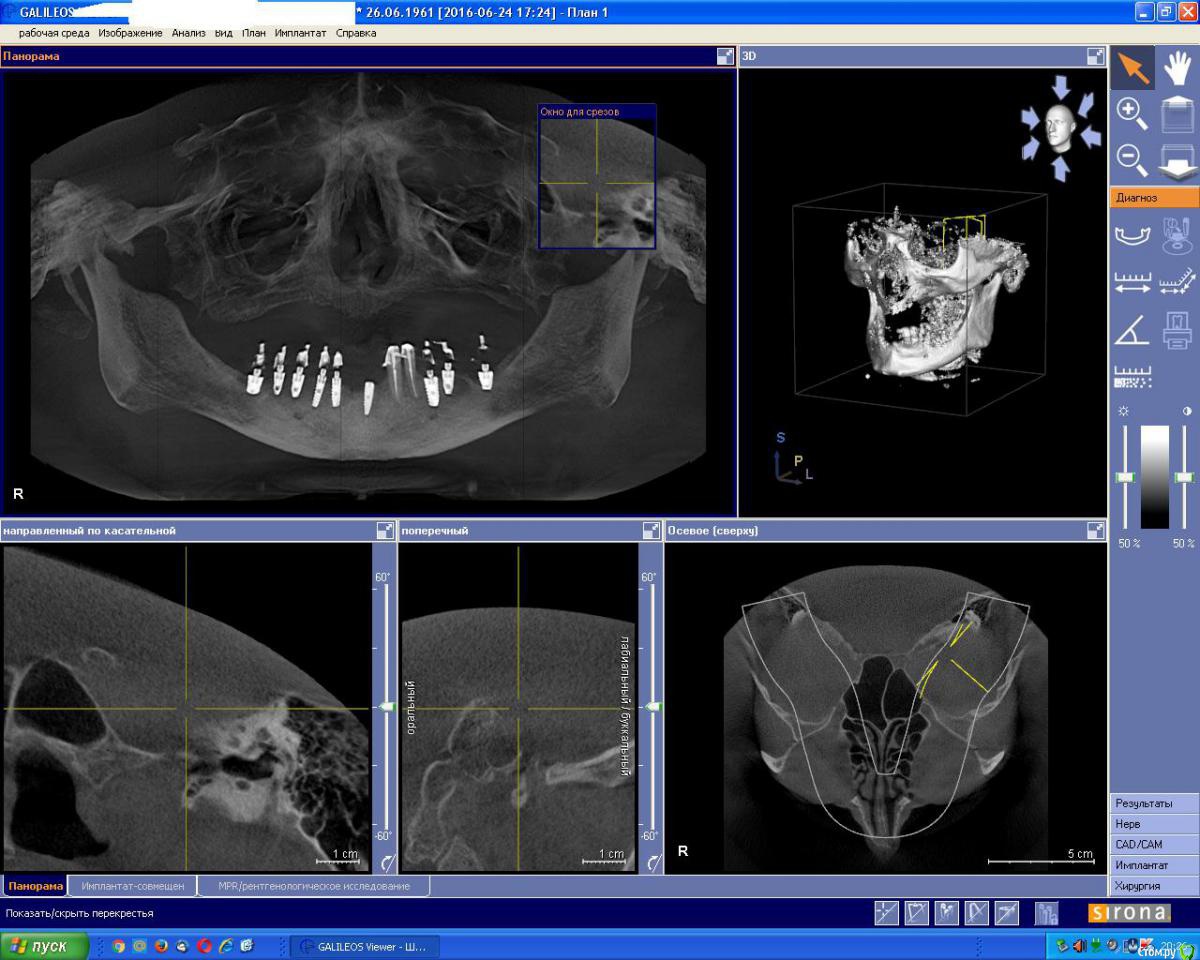

an_ver Опубликовано 25 июня, 2016 Поделиться Опубликовано 25 июня, 2016 Пациент обратился по поводу в\ч..отправил на кт...и вот что увидел на н\ч...пациент уверен что это мк...импланты стоят вроде МИС...что за хрень? 1 год прошел после протезирования Ссылка на комментарий

chervoncevdaniil Опубликовано 25 июня, 2016 Поделиться Опубликовано 25 июня, 2016 Так пластмасса на рг и кт выглядит,а пац может что угодно говорить,не думаю,что доктор такой аферист,чтобы при тотальной работе на имплантах вместо мк сделать пластик,пациент что то недоговаривает 2 Ссылка на комментарий

an_ver Опубликовано 26 июня, 2016 Автор Поделиться Опубликовано 26 июня, 2016 Чеки видел и накладные..там мк стоит...а во рту пластик...писец какой то! Ссылка на комментарий